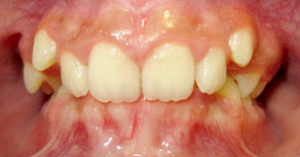

Crossbite

A crossbite occurs when one or more of the upper teeth bite on the inside of the lower teeth. It can occur in the front of the mouth or on the sides, where its usually a bilateral condition. Early correction of a crossbite is recommended because it can lead to permanent problems including asymmetric jaw growth, irregular muscle function and altered tooth eruption.

Before and After photos: Crossbite Treatment